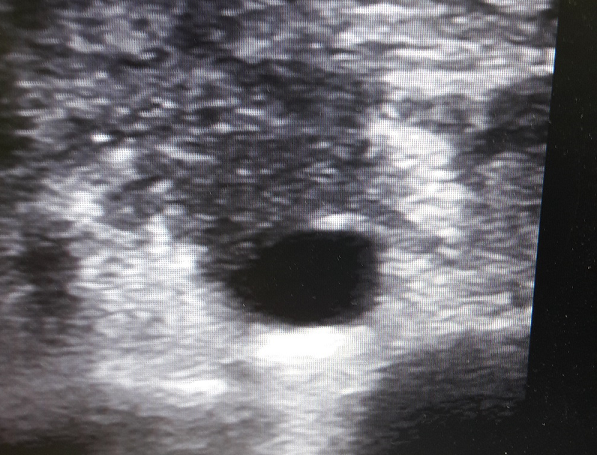

Pancreas is a complex organ with both digestive as well as hormonal functions. With better understanding of its disease profile, various options for treatment of pancreatic disease and cancer must be available. Such services available in GLAD Clinic and its associates include: Pancreatic Tumor Resection (Open, Laparoscopic, Single key-hole) Local ablative therapy (Nanoknife) Minimally invasive Pancreatitis Cyst drainage Systemic therapy